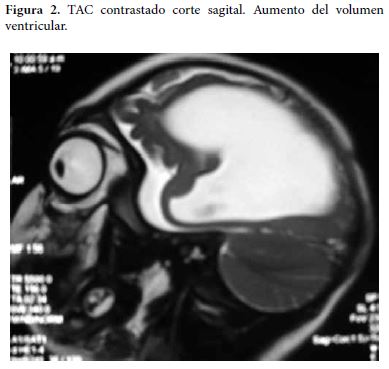

Al examen físico actual se encuentra paciente con peso de 10 kilos, fontanelas cerradas, perímetro cefálico de 41 cms, hiperextensión de cuello y tronco, artrogriposis de las articulaciones de rodillas y tobillos y deformidad en varo de los pies. Se le realiza TAC de cráneo simple y contrastado que muestra dilatación del sistema ventricular con atrofia marcada del parénquima cerebral (Figura 1 y 2).